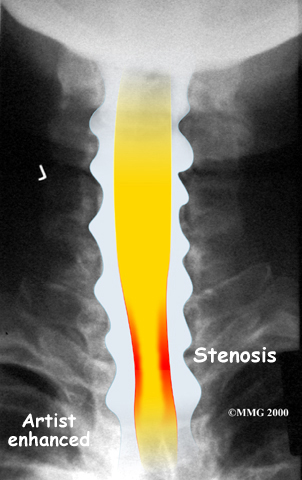

The spinal cord is a column of nerve tissue protected by a bony tube in the spinal column. Conditions that narrow the space in this tube put the spinal cord at risk of getting squeezed. This narrowing is called stenosis. When the narrowing occurs in the spinal column of the neck it is called cervical spinal stenosis, or cervical stenosis. Pressure against the spinal cord as a result of spinal stenosis causes injury to the spinal cord, which is termed myelopathy. Myelopathy is a condition that demands medical attention as it can cause serious problems including problems with the bowels and bladder, changes in the way you walk, and can affect your ability to use your fingers and hands.

The bony spinal canal normally has more than enough room for the spinal cord. Typically, the canal is just less than ¾ of an inch, or 17-18 millimeters around, which is less than the size of a small bottle cap. Spinal stenosis occurs when the canal narrows to around half an inch, or 13 millimeters or less. When the size drops even further, severe symptoms of myelopathy occur. The symptoms of myelopathy result from the actual pressure against the spinal cord itself as well as the reduced blood supply in the spinal cord as a result of the pressure.

Degeneration is the most common cause of spinal stenosis. Wear and tear on the spine from normal aging and from repeated stress and strain can cause many problems in the cervical spine. The intervertebral disc can begin to collapse, shrinking the space between the vertebrae. Bone spurs (small bony projections) may form that protrude into the spinal canal and reduce the space available for the spinal cord. The ligaments that hold the vertebrae together may become thicker and can also push into the spinal canal. All of these conditions narrow the spinal canal.